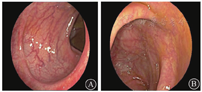

2021年4月13日完善18F-氟代脱氧葡萄糖(18F-fluorodeoxyglucose,18F-FDG)正电子发射计算机体层显像(positron emission tomography and computed tomography,PET/CT)检查示结肠多发节段性18F-FDG代谢增高灶(图1),最大标准摄取值(maximal standardized uptake value,SUVmax)为15.6(降结肠-乙状结肠移行部);肠旁可见多发小淋巴结影,部分18F-FDG摄取略增高;纵隔4R区(右下支气管旁淋巴结)见一增大淋巴结影,大小约为0.9 cm×0.6 cm,18F-FDG摄取增高(SUVmax为2.2),考虑炎症改变;鼻中隔右偏、双下鼻甲肥大;双侧上颌窦炎症;所示诸骨结构完整,未见异常18F-FDG浓聚或缺损灶;其余脏器未见异常18F-FDG摄取。

注:PET为正电子发射体层成像;CT为计算机体层成像;18F-FDG为18F-氟代脱氧葡萄糖;SUVmax为最大标准摄取值;SUVmin为最小标准摄取值;SUVavg为平均标准摄取值;SUVpeak为标准摄取值峰值;SULmax为最大去脂肪标准摄取值;SULmin为最小去脂肪标准摄取值;SULavg为平均去脂肪标准摄取值;SULpeak为去脂肪标准摄取值峰值;TLG为病灶糖酵解总量